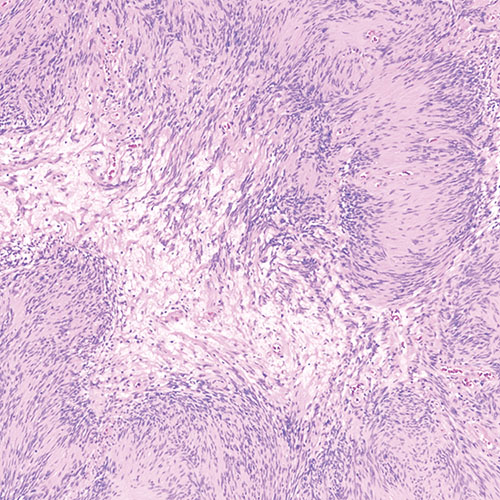

Schwannomas are benign tumors that arise in the peripheral nerves and can spread to the brain. They can cause pain and sometimes nerve damage but are nearly always noncancerous and usually do not grow back after surgery. They’re one of the only tumors whose cells form neatly arranged rows (palisades) and show areas of denser and looser architecture.

Schwannoma under a microscope

Schwannoma